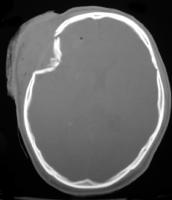

"The fracture was primarily in the center of the scalp defect, and there was marked depression of multiple comminuted fragments of skull.

Bone fragments were obtained from WakeMed pathology and consisted of some 22 pieces of bone in a "bone curettings" labelled container in alcohol. They were removed and pieced together. Following same it is noted that they

represent a 4" x 2" crescent shaped portion of the left parietal and temporal bones with a complex fracture pattern

This devastating wound was a 'depressed' fracture in the center of the 4X2 crushed area of the skull.

Depressed skull fracture

"Depressed skull fractures, as shown in the image below, result from a high-energy direct blow to a small surface area of the skull with a blunt object such as a baseball bat or hammer. Comminution of fragments starts from the point of maximum impact and spreads centrifugally"

Depressed Fracture– a fracture caused by force applied in a ‘focussed’ area e.g. by a hammer. The outer and inner tables of the skull are driven inwards, often causing damage to the brain or its coverings.